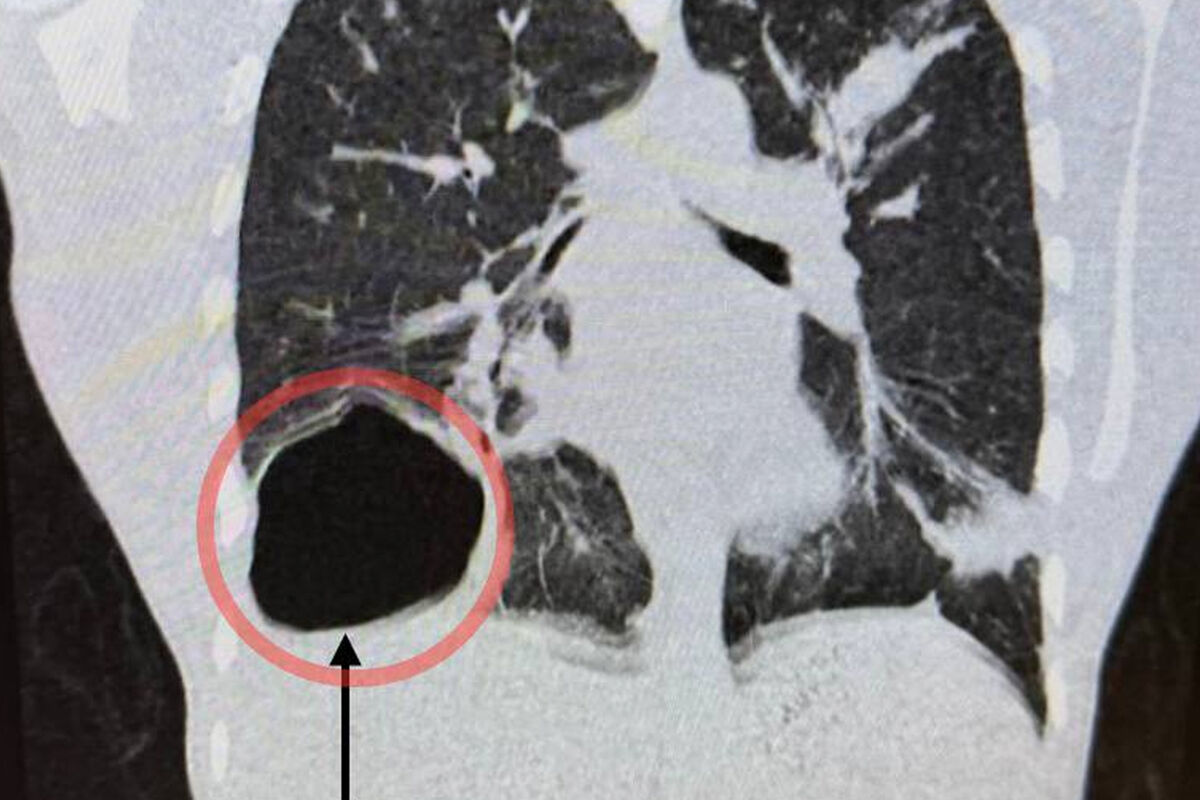

Врачи Московского областного центра охраны материнства и детства (МОЦОМД) спасли 17-летнего подростка с гигантской кистой с паразитами в легком. Об этом сообщили в пресс-службе Минздрава Московской области.

Юноша поступил в больницу с жалобами на недомогание, боль в правой половине грудной клетки и кашель. У него поднялась высокая температура. Обследование показало, что в правом легком находится крупная паразитарная киста.

«Ее размер был сопоставим с размером головы новорожденного ребенка. Киста образовалась из-за попадания в организм гельминта — эхинококка», — поделились медики.